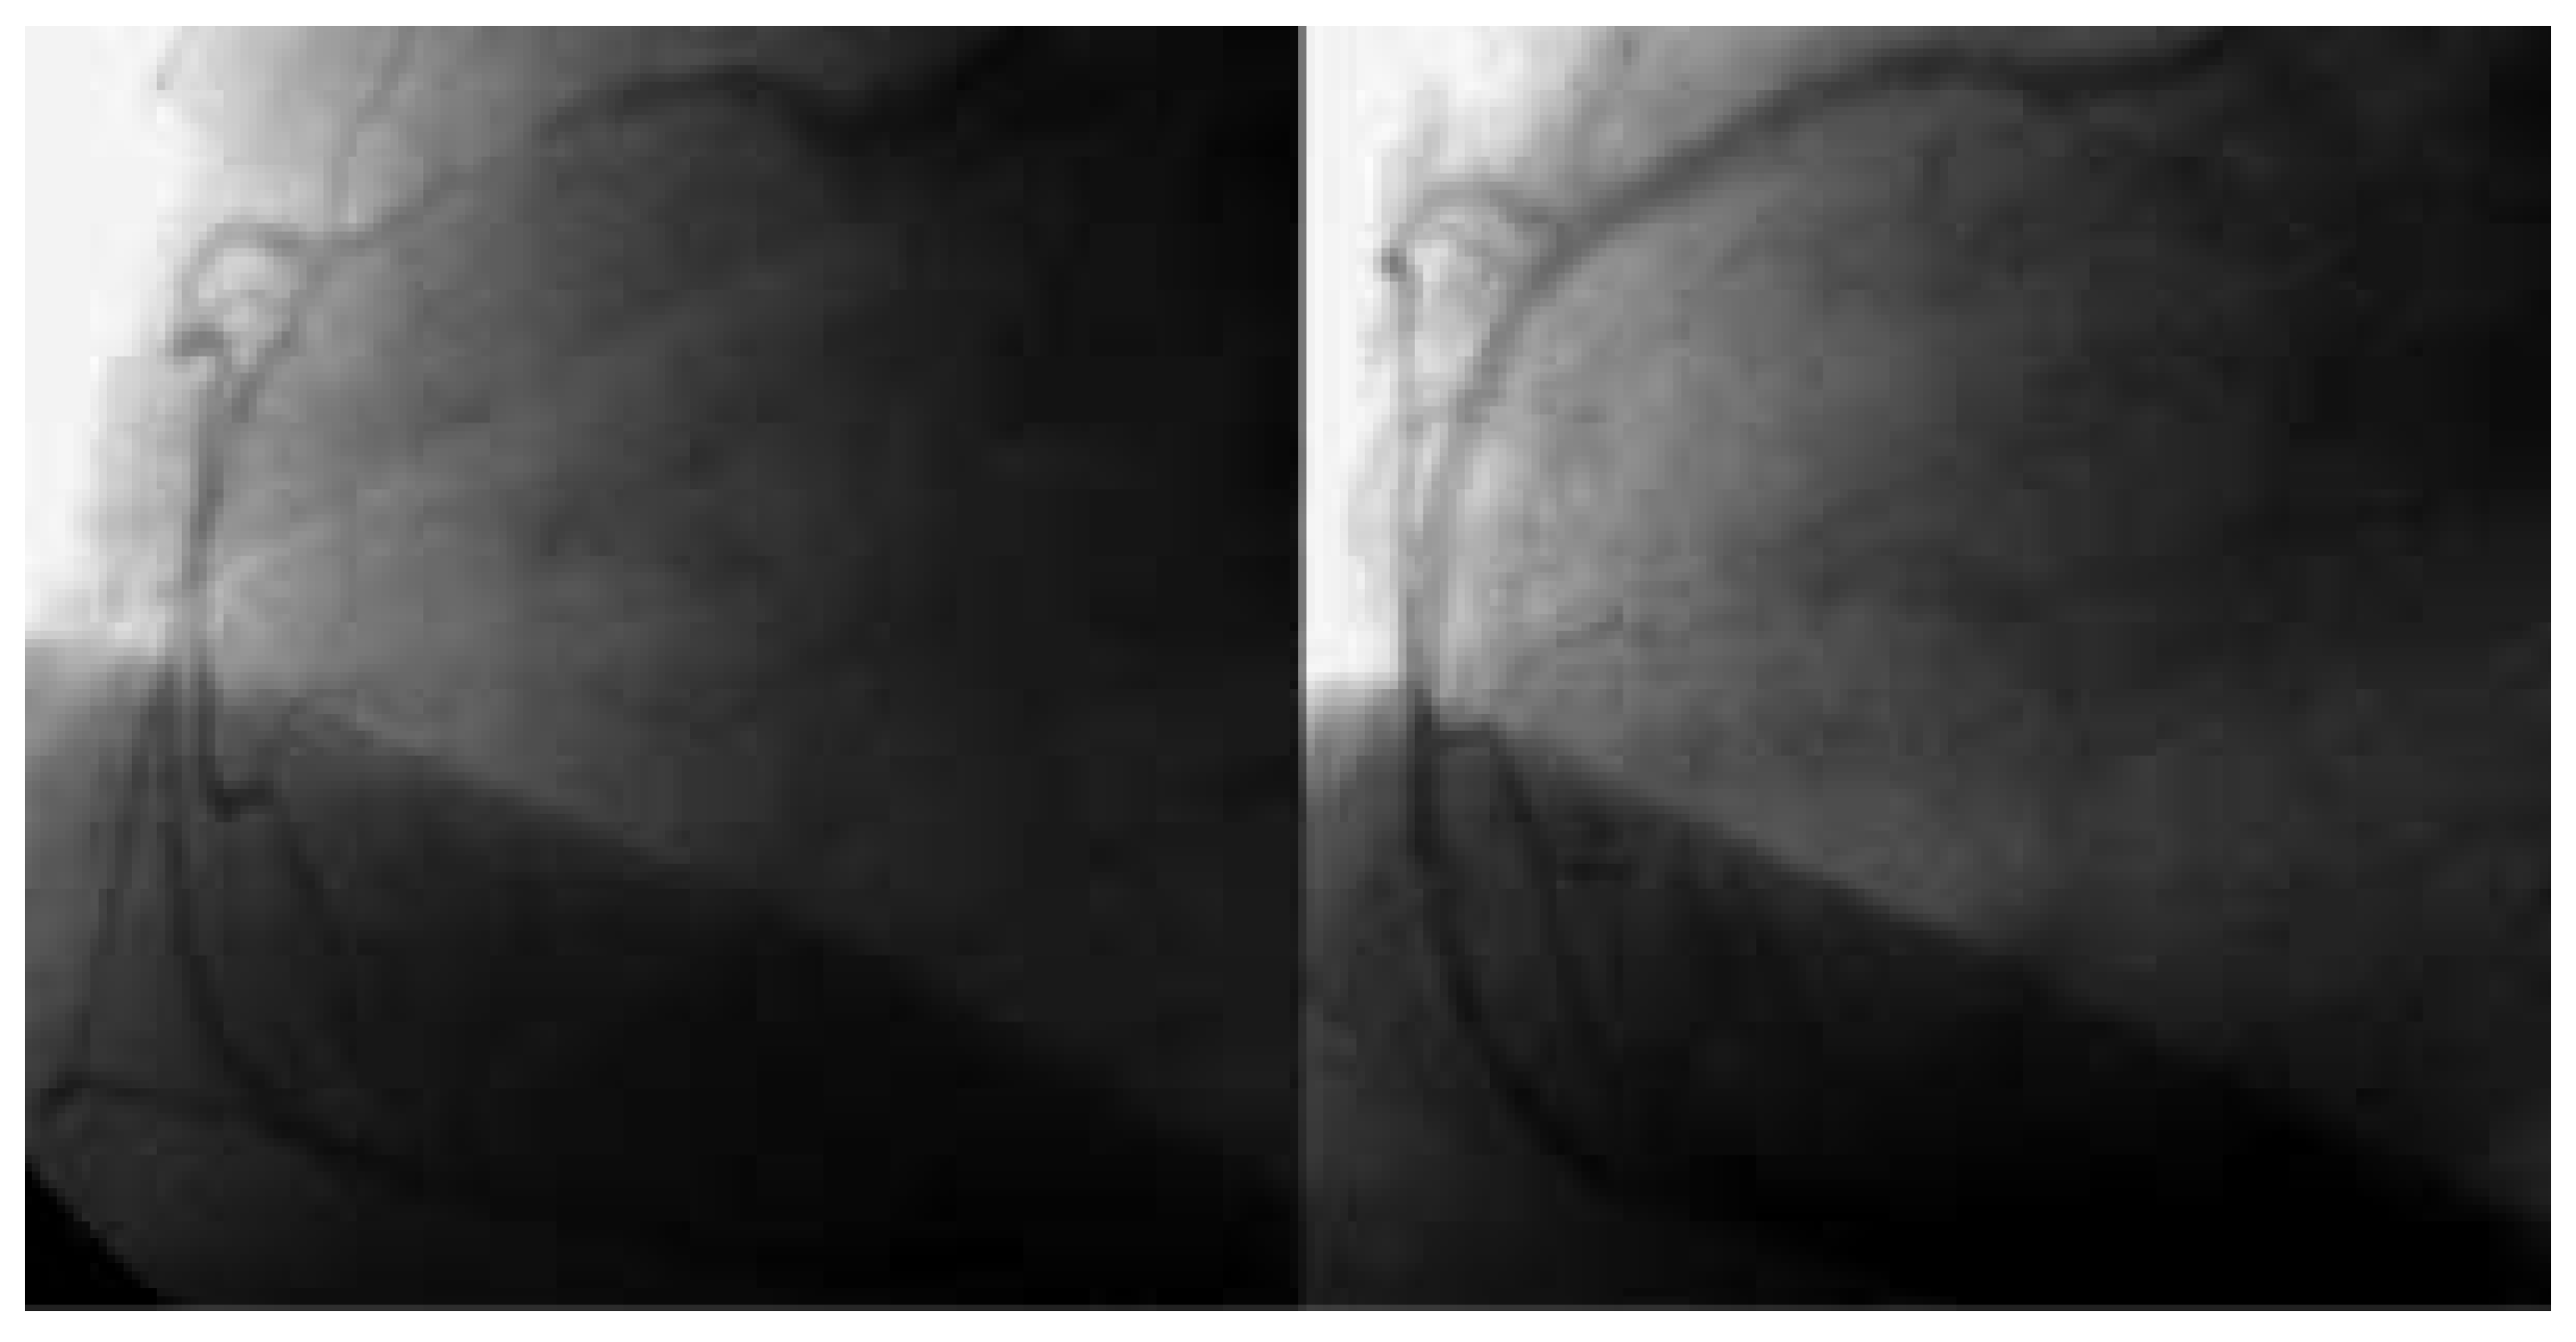

Abbildung 1. Der Linksherzkatheter zeigt eine koronare 3-Ast-Erkrankung mit einem totalen RIVAVerschluss apikal und einem subtotalen Verschluss von RIVA-Mitte (A). Zudem zeigen sich ein chronisch verschlossener RCX und hochgradige ACD-Stenosen mit gutem Fluss. Die RIVA-Mitte wird dilatiert und gestentet (B).

Cardiovascmed 07 00221 g001